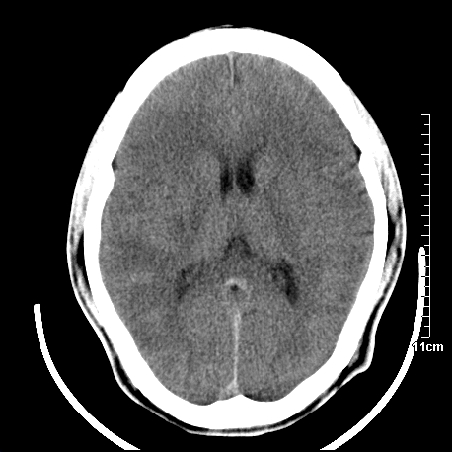

头晕.头痛间断意识恍惚1周 m/21y

右侧放射冠可见点状低密度,可疑腔隙性梗塞

其实现在反过来看,第一次就有点问题,只是什么问题现在还不敢下,一定要做mri ,要不只能观察了

我当时诊断的是1.右侧底节区脑血栓形成

2.考虑少量蛛网膜下腔出血

3.右侧颞叶低密度区考虑脑血管畸形